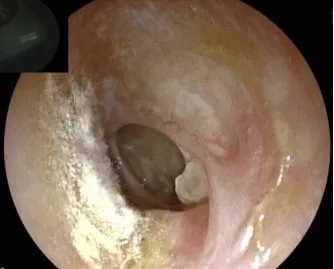

五、真菌性中耳炎(Mycotic otitis media)

真菌性中耳炎(mycotic otitis media)临床并不少见,常与抗菌素滥用有关。主要症状为听力下降、耳溢液、耳痒(尤其夜间时明显)、耳鸣等;耳部检查时,外耳道皮肤常有真菌改变,可见鼓膜穿孔,穿孔边缘或鼓室内有肉芽生长,深部有浆液性或浆液脓性分泌物。对抗细菌感染治疗无效,个别可广泛破坏骨壁,引起颅内并发症。本病的诊断应依据真菌培养和病检结果。真菌性鼓膜炎的治疗基本同真菌性外耳道炎。中耳真菌感染除局部治疗外,部分患者尚需全身应用抗真菌药物,如酮康唑、斯皮仁诺或两性霉素B等治疗。抗真菌药物的肝脏损害副作用大,用药时注意检测肝功能,肝功能损害的患者慎用。

640.webp (1)

图5  真菌性中耳炎耳纤维内镜图。